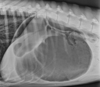

What does the radiograph show?

GDV- after stabilization